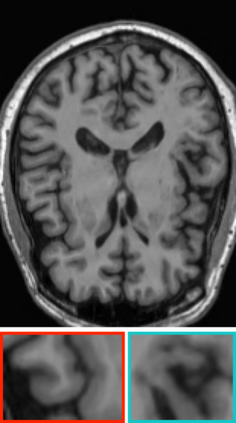

Deep neural networks for medical image reconstruction are traditionally trained using high-quality ground-truth images as training targets. Recent work onNoise2Noise (N2N) has shown the potential of using multiple noisy measurements of the same object as an alternative to having a ground truth. However, existing N2N-based methods cannot exploit information from various motion states, limiting their ability to learn on moving objects. This paper addresses this issue by proposing a novel motion-compensated deep image reconstruction (MoDIR) method that can use information from several unregistered and noisy measurements for training. MoDIR deals with object motion by including a deep registration module jointly trained with the deep reconstruction network without any ground-truth supervision. We validate MoDIR on both simulated and experimentally collected magnetic resonance imaging (MRI) data and show that it significantly improves imaging quality.